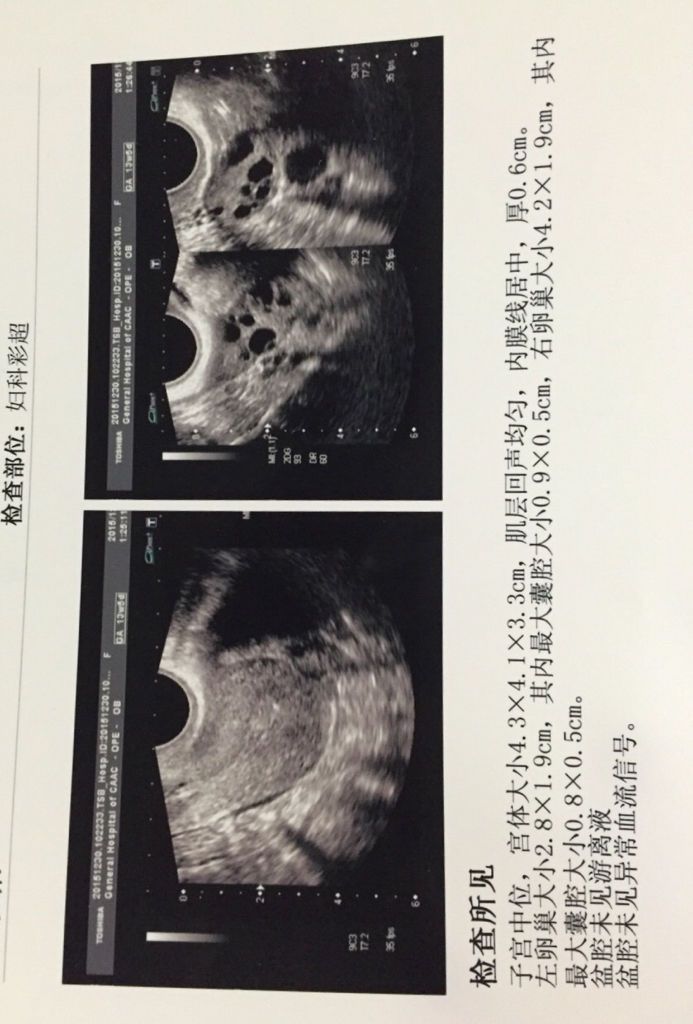

想要宝宝做了孕前检查,其中阴超报告医生说排卵少,有点多囊卵巢什么的,什么意思呢?严重吗?影响要宝宝 想要宝宝做了孕前检查,其中阴超报告医生说排卵少,有点多囊卵巢什么的,什么意思呢?严重吗?影响要宝宝吗?请高手医生给看看。谢谢。本人27周岁。 点击展开 匿名用户 2015-12-31 22:52 满意回答 从超声检查来看卵泡不够寸串圆润,是否能够成概兔吉熟排出还告搂需要后期监测才可以。没看到多囊提示。 东郭灵慧_eGp2 2015-12-31 23:00 宝宝知道提示您:回答为网友贡献,仅供参考。 为您推荐: 其他回答 就是卵子不大好 匿名用户 2015-12-31 22:56 相关问题 在丰城妇产医院孕前检查出多囊卵巢了,这个对身体有什么不好影响吗?会不会影响排卵? 我是多囊卵巢综合症,7月10号来的月经,25测的排卵同房,30号小腹疼痛了一天,请问这是怎么回事? 我是多囊卵巢综合证,孕前吃过二